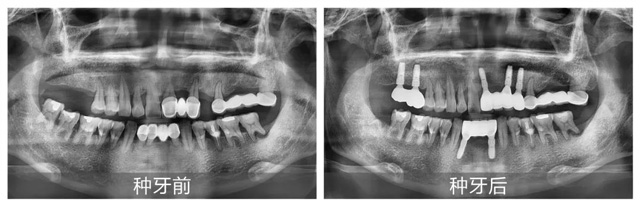

因牙周病的困擾,卞先生僅30多歲牙齒便接連松動(dòng)脫落。2012年曾在伊犁某口腔機(jī)構(gòu)進(jìn)行烤瓷固定橋修復(fù),但受限于當(dāng)?shù)蒯t(yī)療條件,且隨著時(shí)間推移,上下頜前側(cè)的多處修復(fù)體逐漸松動(dòng),加上上頜1顆前牙和右側(cè)2顆磨牙的脫落,導(dǎo)致卞先生的咀嚼功能?chē)?yán)重受損。

經(jīng)CBCT全景檢查所見(jiàn),謝海洋主任發(fā)現(xiàn)卞先生存在多顆牙缺失、殘存牙體伴有嚴(yán)重骨吸收,且多顆修復(fù)體失效等問(wèn)題,亟待通過(guò)種植牙重建咬合功能。針對(duì)顧客異地就醫(yī)、就診時(shí)間有限的情況,謝海洋主任為卞先生制定了“上下頜多顆即拔即種+連冠修復(fù)”的個(gè)性化種植方案:下頜種植2顆基牙支撐2顆連冠,上頜右側(cè)種植2顆獨(dú)立基牙,上頜前側(cè)種植3顆基牙連冠修復(fù)1顆。